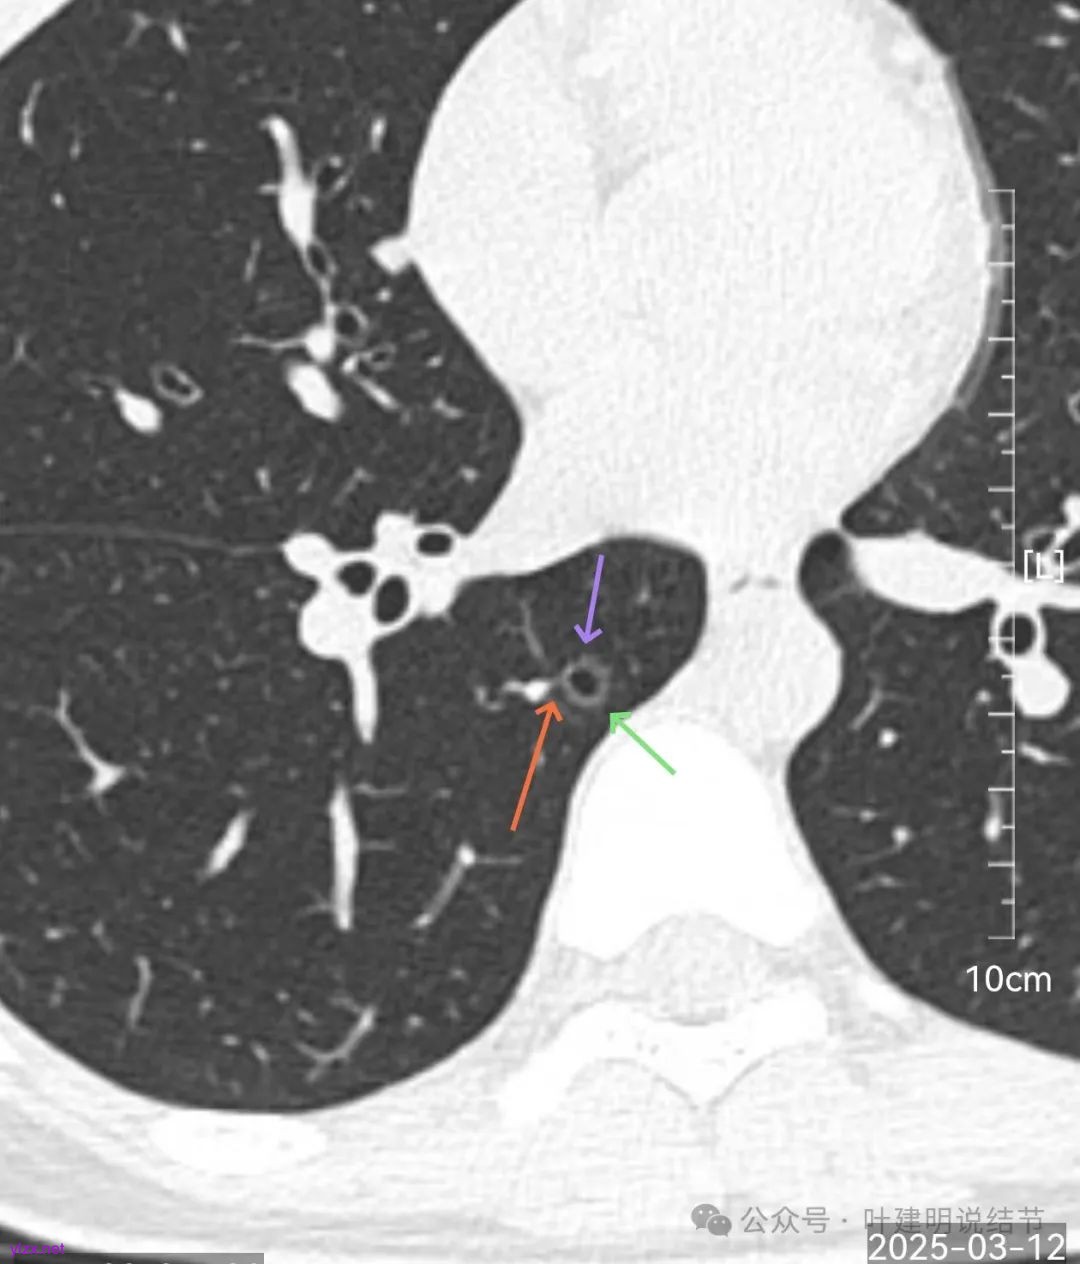

病灶6:右下叶脊柱旁囊腔型病灶,整体轮廓与边界清,没有明显实性成分,考虑原位癌或微浸润性腺癌可能性大。

再来看风险最大的病灶6的连续层面:

血管从旁过,没有受结节影响。